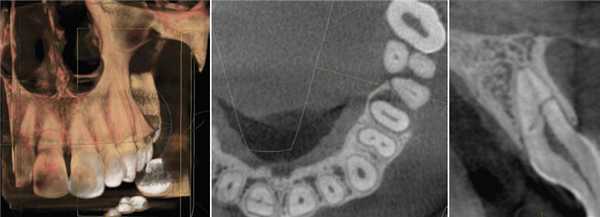

Классически предполагалось, что внутренняя резорбция витальных зубов развивается из-за травматического поражения пульпы (фото 1), а внешняя резорбция случается строго в девитальных зубах (фото 2). К последней могут привести травма периодонтальной связки вследствие воздействия внешних факторов, давления, которое возникает в результате прорезывания зубов, или же патологии развития (фото 3). Иногда внешняя резорбция наблюдается после проведенного ортодонтического лечения, которое провоцирует повышении активности остеокластов в области цемента и дентина верхушки корня. Большинство врачей конечно же полагаются на знания, полученные в ходе предварительного обучения, но некоторые все же интересуются динамикой развития доказательных фактов относительно тех или иных стоматологических патологий.

Фото 1. Рентгенограмма, демонстрирующая пример внутренней резорбции корня.

Фото 2. Рентгенограмма, демонстрирующая пример внешней воспалительной резорбции корня.

Фото 3. Рентгенограмма, демонстрирующая пример резорбции по причине давления.

В течение последних двух десятилетий в стоматологической литературе была представлено значительное количество публикаций, описывающих уникальные случаи внешней резорбции полностью витальных зубов в области шейки. Следовательно, данную разновидность патологии пришлось добавить к двум уже ранее известным (фото 4). Иногда термины для описания данного вида поражения носят лишь субъективный характер, но для четкого понимания в данной статье будет использоваться название инвазивная пришеечная резорбция корня (ИПРК), поскольку именно такое название данной патологии дал доктор Geoffrey S. Heithersay, который и описал ее первично. В данной статье будет рассмотрены как клинические, так и рентгенологические признаки резорбции, а также аспекты, связанные с ее этиологией, патофизиологией и лечением.

Фото 4. Рентгенограмма, демонстрирующая пример инвазивной пришеечной резорбции.